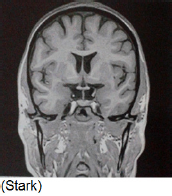

De acordo com a imagem a seguir, assinale a alternativa que determina a secção de corte.